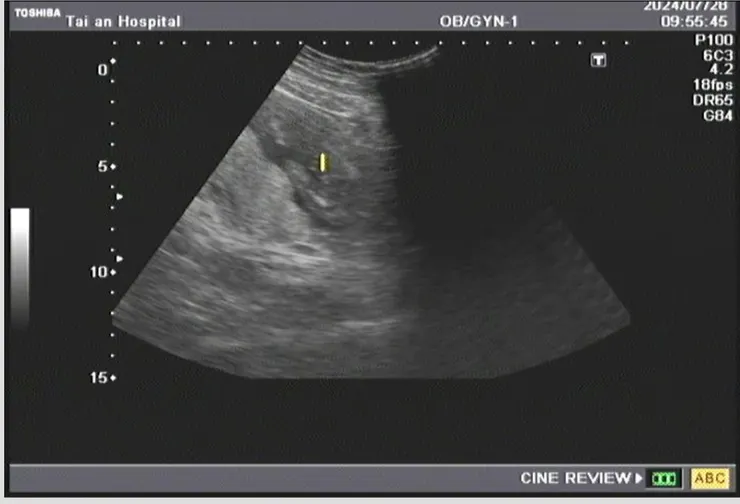

後來去了婦產科證實了二寶的存在

上次去檢查,醫生說,有很大的機率是男寶~